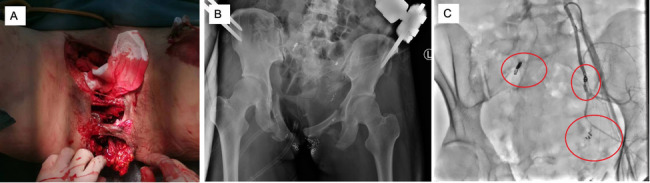

Methods: We retrospectively analyzed clinical data from 32 polytrauma patients with pelvic fractures managed under an integrated multidisciplinary treatment protocol in our trauma center's Emergency Intensive Care Unit (EICU). This protocol incorporated expedited prehospital transport, trauma team activation before patient arrival, "resuscitation in the operating room" strategy, and collaborative intervention from emergency surgery, trauma surgery, interventional radiology, and EICU teams. We collected patient demographics, injury characteristics, therapeutic interventions, and outcome data. Univariate and correlation analyses were employed to identify mortality risk factors.

Results: The study cohort (n = 32) had a mean age of 51.2 ± 18.3 years, with female predominance (62.5%). Motor vehicle accidents constituted the primary injury mechanism (75.0%). Thoracic injuries were the most prevalent concomitant injuries (87.5%). Under the multidisciplinary collaborative approach, 37.5% of patients underwent early external pelvic fixation, and 6.3% received transcatheter arterial embolization (TAE). Surgical interventions significantly reduced pain scores (p < 0.001). The overall mortality rate was 9.4% (3/32). Correlation analysis demonstrated a negative association between mortality and Glasgow Coma Scale (GCS) scores (-0.710) and a positive correlation with Injury Severity Score (ISS) (0.547).